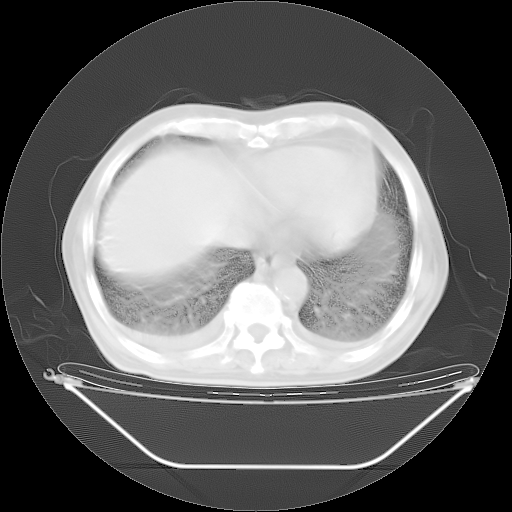

今天复查肺部CT,发现双肺广泛磨玻璃样改变。所以我把3月19日和5月9日相隔50天的肺部CT上传。请大家会诊。

5月9日肺部CT(在4月27日齐鲁医院肺部CT描述部分肺组织磨玻璃样改变,12天后肺组织广泛磨玻璃样改变)

2009年5月9日肺部CT